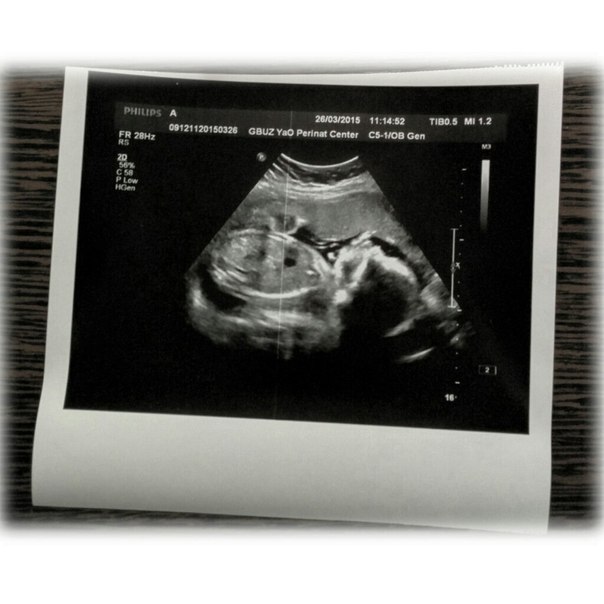

Не буду ходить вокруг да около, на УЗИ нам подтвердили девочку, нашу сладенькую булочку, ну по-другому просто и быть не могло. Все счастливы, особенно муж!!! Развиваемся мы хорошо, даже отлично. На первом скрининге разница с акушерским сроком была ровно на неделю, а сейчас на 3 дня даже опережаем) Как я счастлива была увидеть нашу девочку, нашу красавицу, моя любовь к ней просто не знает границ! У нас папин носик, обычно все девочки похожи на отцов:) Вот какие мы

Данные по УЗИ: БПР 56мм, ЛЗР 68мм, ОГ 195мм, ОЖ 182мм

Плацента 0 степени зрелости, что не может не радовать, кол-во амниотической жидкости - нормальное!